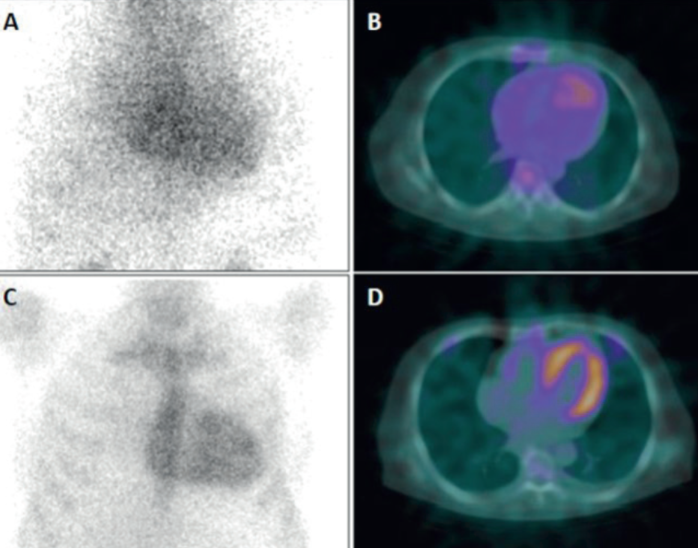

Como en todo método diagnóstico, el centellograma puede tener resultados falsos positivos y falsos negativos que deben considerarse (tabla 2). Los primeros se vinculan a algunos tipos de amiloidosis AL (AApoAI, AApoAII, ApoAIV y Aß2M), que generalmente están asociadas a compromiso renal. Otras causas de falsos positivos, como la persistencia del radiotrazador en el espacio vascular, fracturas costales, calcificaciones valvulares, infarto de miocardio reciente (menor a 4 semanas), pueden ser en general identificadas mediante SPECT o mediante técnica híbrida SPECT/CT (figura 3). También se ha descrito captación miocárdica incidental en otras condiciones como la enfermedad de Chagas, cardiotoxicidad por hidroxicloroquina, miocarditis, trauma cardíaco y cardioversión reciente(11,25). En cuanto a los falsos negativos, pueden darse en algunos subtipos raros de la ATTR hereditaria como la Pne84Leu-ATTRv o la Ser97Tyr-ATTRv, que concomitan con neuropatía y enfermedad familiar y se identifican mediante pruebas genéticas. Otras causas de falsos negativos son la afectación cardíaca leve o incipiente y ciertos aspectos técnicos como la precocidad o el retraso en la adquisición de las imágenes; todo esto destaca la necesidad de un adecuado grado de experticia para la realización e interpretación del estudio(9).

A) Imagen planar de tórax que muestra captación de 99mTc-PYP en el área cardíaca, en forma difusa (Perugini 1 2). B) SPECT/CT en plano transaxial confirma que la captación corresponde al pool sanguíneo y no a la pared miocárdica (negativo para ATTR). C) Captación cardíaca relativamente definida en la imagen planar (Perugini 2). D) SPECT/CT demuestra claramente la captación miocárdica (cortesía Dr. Gabriel Grossman, Porto Alegre).